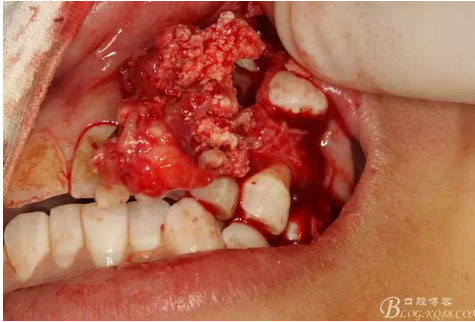

圖17.呼之欲出的巨大牙瘤組織。

圖18.摘除囊腫后遺留的巨大骨腔